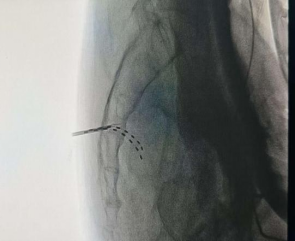

今年3月,田主任先为欧先生采用经皮穿刺技术成功植入临时电极,并通过电生理监测系统实时观察植入部位及患者的反应。术中测试显示应答反应佳,手术过程顺利。在术后测试体验治疗阶段,该团队通过精细调整刺激参数,密切观察症状,欧先生会阴区疼痛得到了显著缓解,患者及家属对测试期治疗效果表示高度满意,并积极愿意接受骶神经电刺激永久植入术,以进行长期的系统性治疗。田主任团队已成功为欧先生实施了骶神经电刺激永久植入术。术后,欧先生疼痛程度较术前显著减轻,睡眠和生活质量得到大幅提升,重新恢复了社交信心。家属深有感触地表示:“从没见过他如此轻松过。”

田文海主任团队手术中